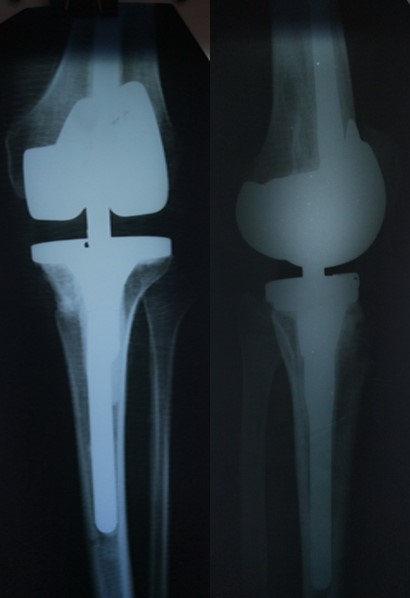

Приклад 4. Хвора Г. 72 років. Діагноз: Деформівний IV ст. гонартроз, стан після ТЕП КС (2010р.). Гемартроз в післяопераційному періоді, хронічний синовііт.Септична нестабільність компонентів ендопротеза  колінного суглоба на протязі року. Виявлений дефект виростків стегнової кістки  тип Т3, F 3 за класифікацією АОRI [G.A. Engh, C.H. Rorabeck, 1997]. Хворій виконано  двоєтапне ревізійне ендопротезування: видалення компонентів ендопротезу іплантовано спейсер з антибіотиком. Піcля санаціїї виконано другий єтап певізії, імплантовано ревізійний ендопротез колінного суглоба.